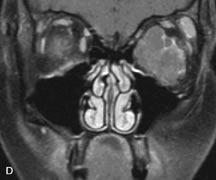

Pleomorphic adenomas demonstrate long T1 and T2 signal characteristics. They may show heterogeneity on T2-weighted images74 and moderate to marked enhancement with contrast.75 Signal characteristics of adenoid cystic carcinoma include hypointensity to fat on T1-weighted images, hyperintensity to fat with increased T2 weighting, and isointensity to fat on proton density-weighted studies (Fig. 23).31,75 Secondary bony alterations of the lacrimal fossa associated with lacrimal gland tumors, such as remodeling (benign mixed tumor) or destruction (adenoid cystic carcinoma), are seen indirectly on MR images; however, bone windows on CT scans provide better delineation of these changes. In contrast to the round or globular appearance of benign or malignant epithelial tumors of the lacrimal gland, lymphoproliferative tumors usually appear to be molding or draping onto the globe and the surrounding bony orbit.

Fig. 23. A. T2-weighted and (B and C) postcontrast fat-suppressed T1-weighted MR scans demonstrate an infiltrative lacrimal region mass than invades the lateral rectus muscle (arrows). This highly cellular lesion is seen to have a very hypointense appearance on the T2-weighted scan.